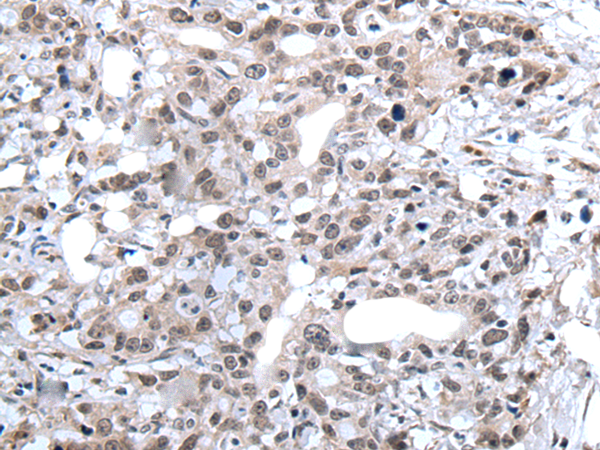

分类: 科研抗体货号: P12818别名: ATG1; ATG1A; UNC51; hATG1; Unc51.1应用: IHC反应种属: Human